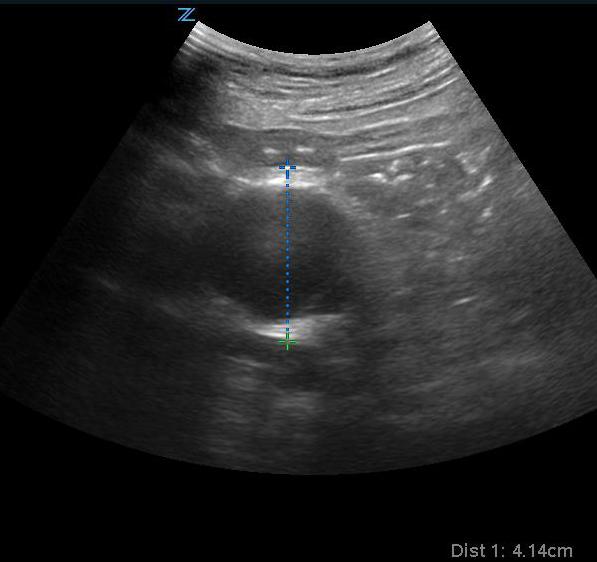

Ultrasound By Emergency Physicians To Detect Abdominal Aortic Aneurysms A Uk Case Series Emergency Medicine Journal

Sonoguide Abdominal Aortic Aneurysm